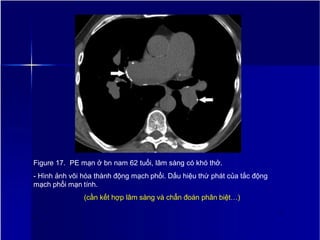

Figure 17. PE mạn ở bn nam 62 tuổi, lâm sàng có khó thở.

- Hình ảnh vôi hóa thành động mạch phổi. Dấu hiệu thứ phát của tắc động

mạch phổi mạn tính.

(cần kết hợp lâm sàng và chẩn đoán phân biệt…)